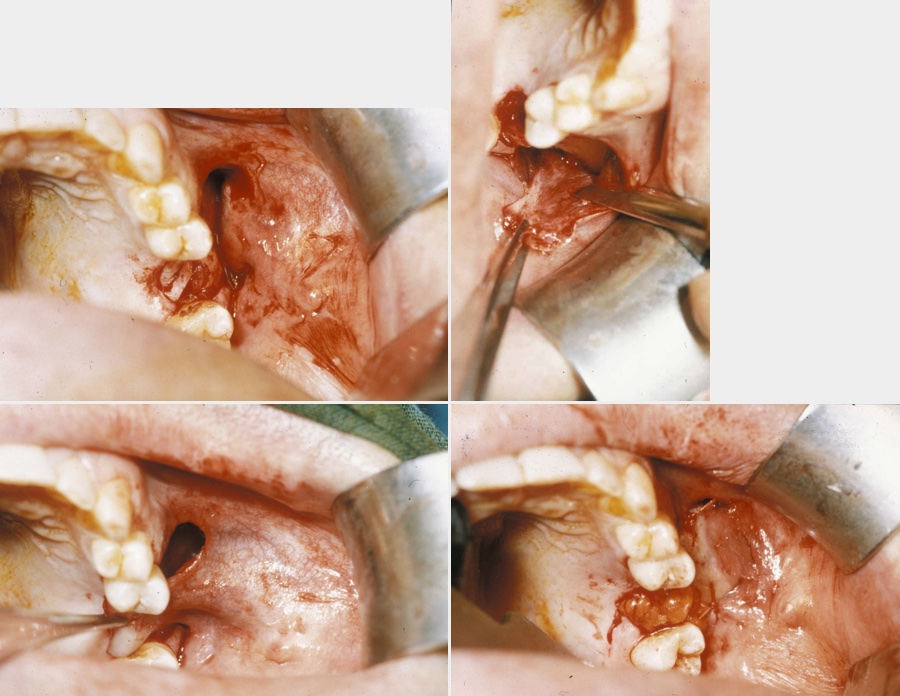

This procedure is approached using a similar incision to the buccal advancement flap (see above), but when the periosteum is incised, an artery clip is passed into the submucosa to identify the buccal fat pad (Figure 3).

Figure 3: The buccal pad of fat, a vascularised mobilizable entity which can be repositioned as a flap.

This is an axial flap that lends itself beautifully to the closure of oroantral fistulae. It can be used as an isolated flap where the vascularised fat fills the defect and is held in place with vertical mattress sutures (common, interrupted suture technique designed for minimal tension and scarring), thus allowing the raised buccal flap to be repositioned in the buccal sulcus to maintain depth (Figure 4).

Figure 4: Top left: Technique for buccal fat pad flaps – relieving incisions; top right: subperiosteal flap elevated; middle left: buccal fat pad exposed by periosteal incision; middle right: fat pad delivered and used as sole reconstruction to maintain sulcus depth; bottom: postoperative healing showing preserved cheeks and sulcus.